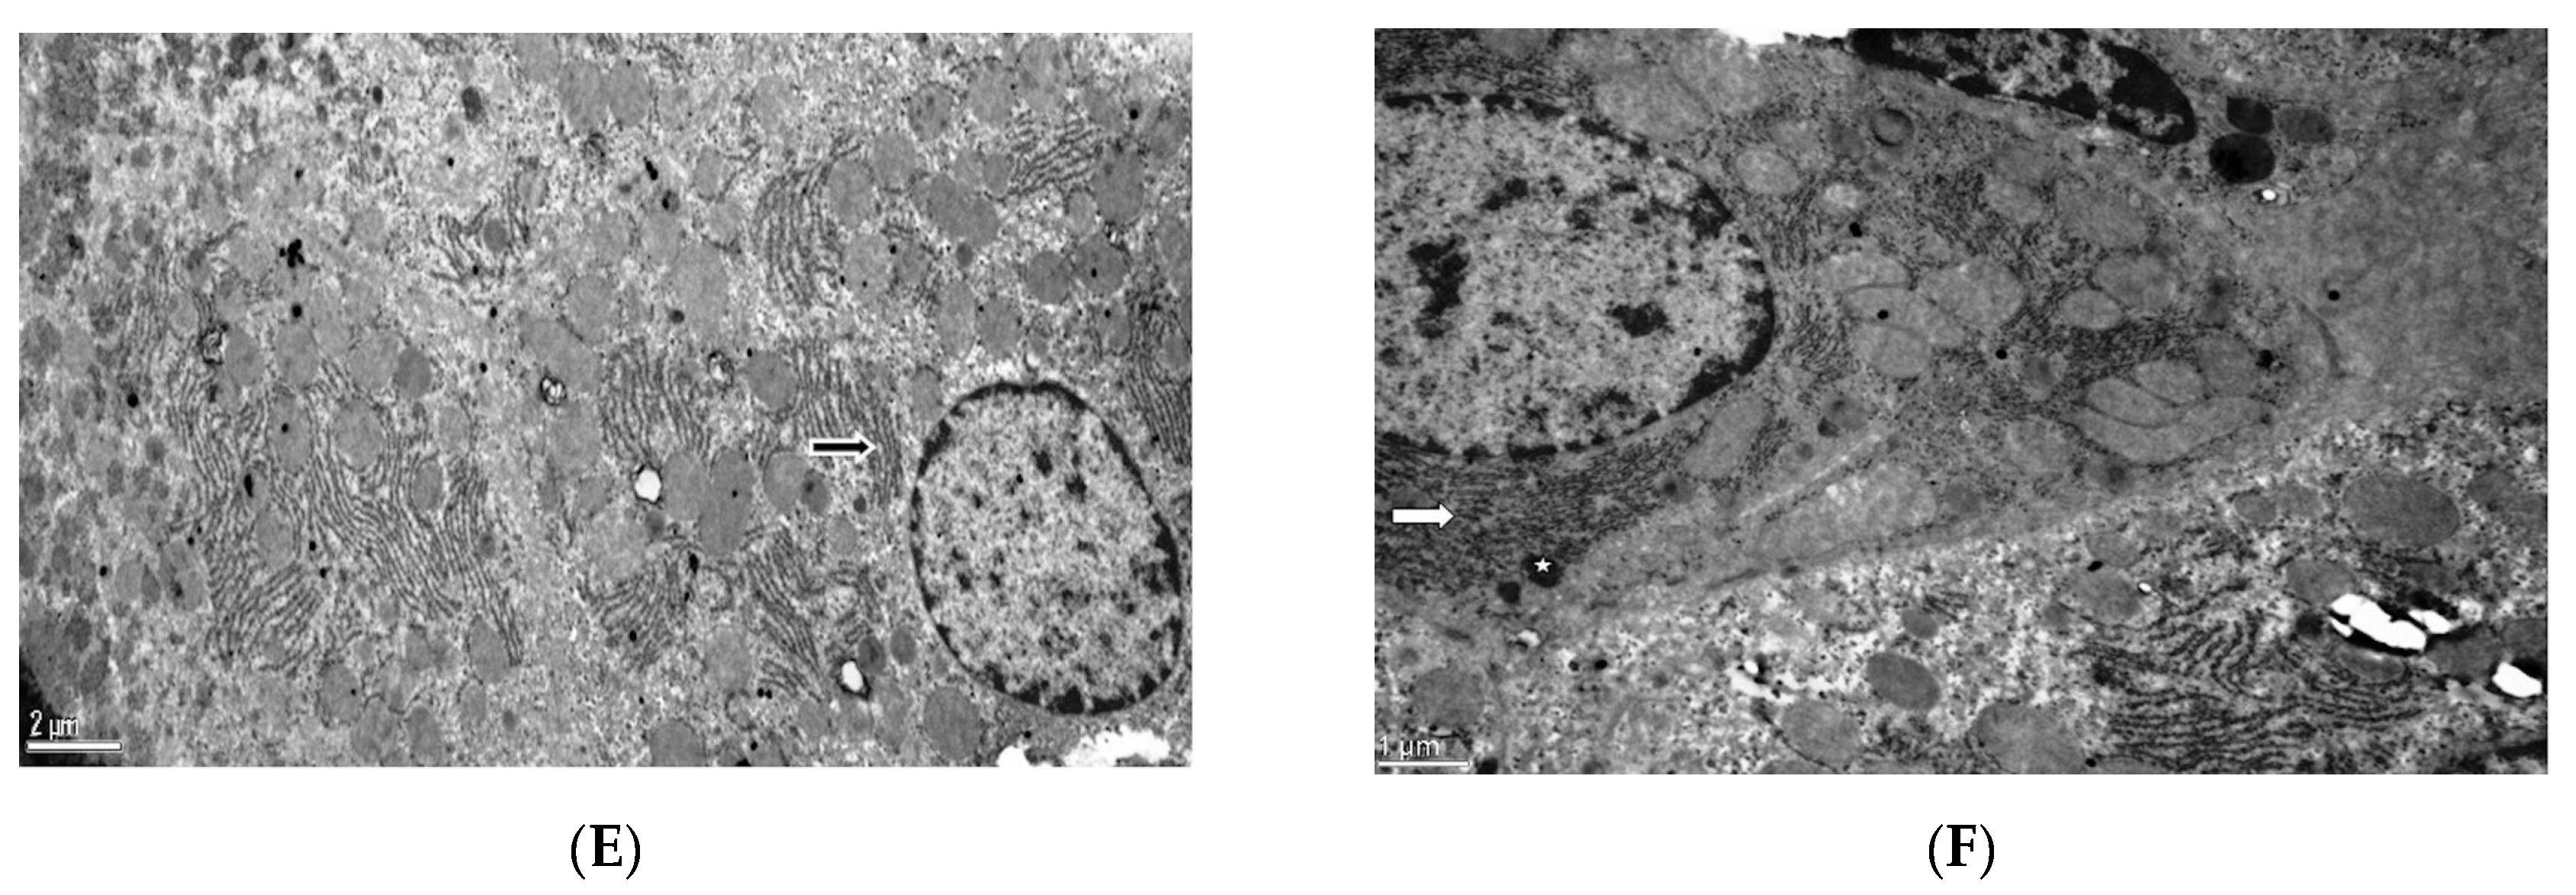

Electron Microscopic Features: In the control group, there were healthy-appearing hepatocytes with patent sinusoids and normal nuclear and cytoplasmic features as well as Kupffer cells and Ito cells with fat droplets. Cellular characteristics in the tau group were similar to those in the control group. In the group treated with doxorubicin, both large numbers of fat vacuoles in hepatocytes and the enlargement of nuclear pores in hepatocytes and Kupffer cells were observed. The rough endoplasmic reticulum had a scattered appearance in the cytoplasm. On the other hand, in the dox+tau group, the rough endoplasmic reticulum formed clumps and was located close to the nucleus, as observed in the control group (Figure 2).

Figure 2.

Electron microscope image of liver tissue. (A) Control group, arrowhead: hepatocyte nucleus, asterisk: Ito cell with fat droplets, and arrow: collagen fibers [×6000]. (B) Taurine group, arrow: hepatocyte nucleus and asterisk: Kupffer cell nucleus [×2500]. (C) Doxorubicin group, rER: tough endoplasmic reticulum and arrow: rER [×8000]. (D) Doxorubicin group, arrow: nuclear pore and asterisk: fat vacuoles [×12,000]. (E) Doxorubicin+taurine group, arrow: rER [×8000]. (F) Doxorubicin+taurine group, arrow: rER and asterisk: heterophagic vacuoles. [×15,000]. rER: rough endoplasmic reticulum.

Taurine may have exerted this effect by regulating Na+–K+ ATPase and Ca+2 -ATPase activities. Doxorubicin administration reduces the activity of these enzymes, resulting in membrane damage [34]. Therefore, this finding may be due to the fact that taurine provides membrane stabilization in hepatocytes, preventing ion leakage and water influx, thus protecting the cell from swelling [35]. Another possible mechanism may be the inhibition of intrinsic (mitochondrial), extrinsic receptor-mediated, and apoptotic pathways such as the endoplasmic reticulum. Doxorubicin administration causes an increase in Fas, caspase-8, and Bax levels and a decrease in Bcl-2 levels and mitochondrial membrane potential. Taurine treatment prevents these changes [34]. In addition, the increase in active calpain 1 (protein level) and caspase-12 (protein level) and the intracellular calcium concentration return to normal levels with taurine administration [34]. Electron microscopy images from this study show that taurine protects cellular structures such as the endoplasmic reticulum. Increased intracellular calcium is known to cause disruption of the structure of the endoplasmic reticulum [36]. In our study, the correction of dox-induced intracellular organelle perturbations by taurine treatment demonstrated the importance of taurine in calcium homeostasis. Although this study is the first to demonstrate the protective role of taurine in dox-induced hepatotoxicity by electron microscopy, we did not measure intracellular calcium concentrations which is a limitation of our study.